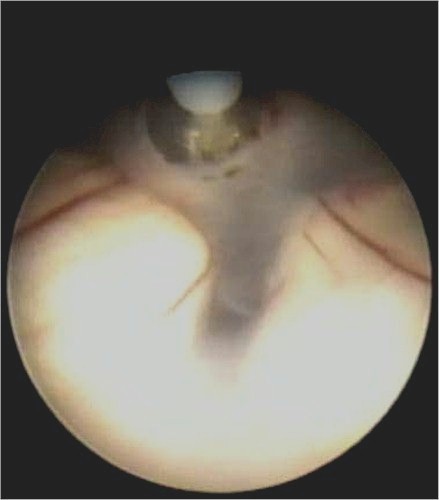

Un selezionato numero di pazienti, in cui l'idrocefalo è ostruttivo, può essere trattato con una procedura alternativa chiamata ventricolocisternostomia.

In questa procedura, un neuroendoscopio (cioè uno strumento che permette all'operatore di visualizzare, tramite una piccola telecamera, le cavità ventricolari sfruttando la tecnologia delle fibre ottiche) viene introdotto nelle cavità ventricolari attraverso un piccolo foro della teca cranica. Si esegue poi con apposito strumentario miniaturizzato, una piccola comunicazione fra il pavimento del terzo ventricolo e gli spazi subaracnoidei della base cranica. Questo permette di bypassare la sede ostruttiva a livello dell'acquedotto o del IV ventricolo.

L'intervento è in anestesia generale. La procedura è miniinvasiva e questo comporta una degenza ospedaliera molto breve. |

Ventricolocisternostomia

(VCS) |

Un selezionato numero di pazienti può essere trattato con una procedura alternativa chiamata ventricolocisternostomia. In questa procedura, un neuroendoscopio (cioè uno strumento che permette all'operatore di visualizzare, tramite una piccola telecamera, le cavità ventricolari sfruttando la tecnologia delle fibre ottiche) viene introdotto, con tecnica stereotassica, nelle cavità ventricolari attraverso un piccolo foro della teca cranica. Lo scopo è quello di realizzare con apposito strumentario miniaturizzato, una piccola comunicazione fra il pavimento del terzo ventricolo e gli spazi subaracnoidei della base cranica.

L'intervento è in anestesia generale. La degenza è breve. |